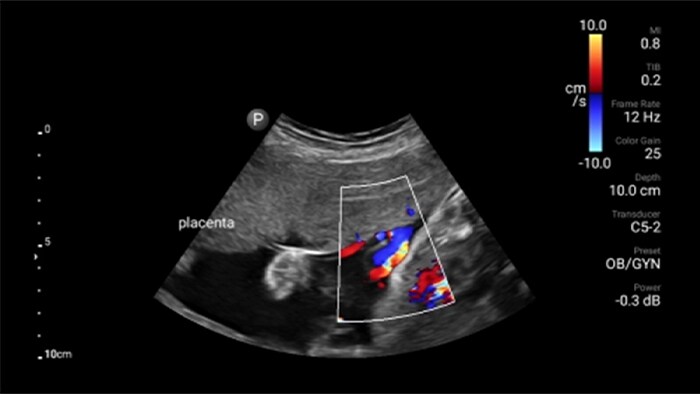

• 5 to 2 MHz extended operating frequency range • 50mm radius of curvature • 2D, color Doppler, M-mode, advanced XRES and multivariate harmonic imaging, SonoCT • High-resolution imaging for deeper applications: abdominal, gall bladder, OB/GYN and lung imaging preset optimizations • Center line marker • USB-C transducer with replaceable cable